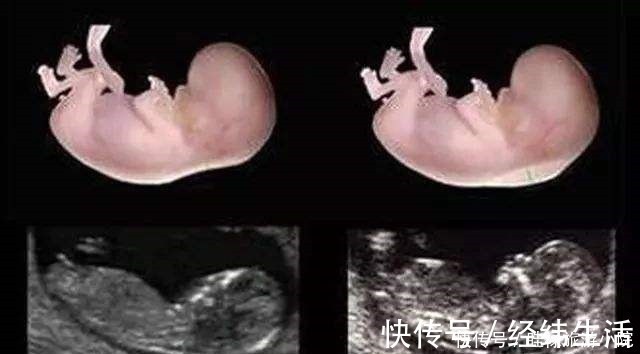

检查时间:怀孕中期,一般是在怀孕16周产检做。唐氏筛查简称唐筛,主要是对胎宝宝是否有“21-三体综合征”进行一次全面筛查,检查方法是抽血。如果唐筛结果显示:临界值或高风险,孕妈们也先别慌。这样的结果 不能证明宝宝就一定会出现唐氏综合征,一般医生会建议进一步做无创DNA检测或羊水穿刺检查进行排查,这两项检查的结果更准确些。由于羊水穿刺检查存在感染的可能,因此无创DNA的使用更广泛些,也是通过抽血的方式检查,对孕妈几乎没有伤害。